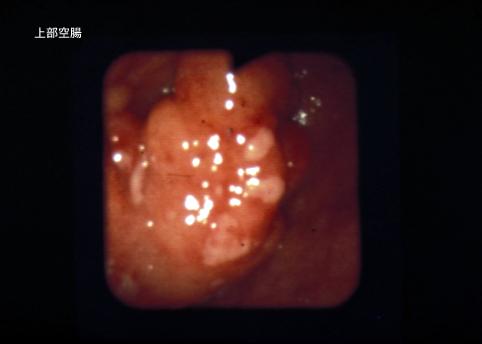

림프계종양 악성림프종 (소장)

소장을 중심으로 다발융기를 주체로 한 악성 림프종---1970년대의 증례

[Image-ID:5515]

악성 림프계종양/악성 림프종

소장/공장

검사방법

종양의 최대경(밀리미터)

10~14

다발종양(동일 장기)

유(동시성)

다중종양(다수의 장기)